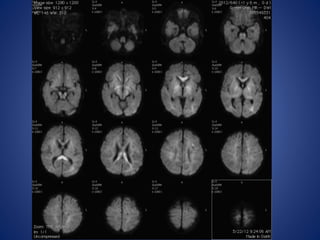

13 yrs male, with history of seizures with cilinical suspicion of febrile

encephalitis.

DWI

ADC

IR

13 yrs male,with history of seizures with cilinical suspicion of febrile encephalitis.